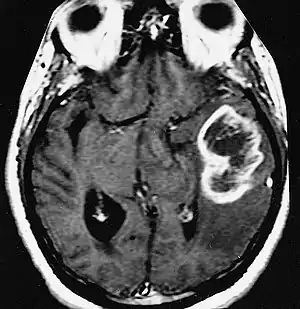

An example of a ring-enhancement around a lesion in gliobastoma. In tumefactive multiple sclerosis, the ring-enhancement is open, not forming a complete ring.

These atypical lesion characteristics include a large intracranial lesion of size greater than 2.0 cm with a mass effect, edema and an open ring enhancement. A mass effect is the effect of a mass on its surroundings, for example, exerting pressure on the surrounding brain matter. Edema is the build-up of fluid within the brain tissue. Usually, the ring enhancement is directed toward the cortical surface.[2] The tumefactive lesion may mimic a malignant glioma or cerebral abscess causing complications during the diagnosis of tumefactive MS. T2-hypointense rim and incomplete ring enhancement of the lesions on post-gadolinium T1- weighted imaging on brain MRI enable accurate diagnosis of TDL[3]

Diagnosis of tumefactive MS is commonly carried out using magnetic resonance imaging (MRI) and proton MR spectroscopy (H-MRS). Diagnosis is difficult as tumefactive MS may mimic the clinical and MRI characteristics of a glioma or a cerebral abscess. However, as compared to tumors and abscesses, tumefactive lesions have an open-ring enhancement as opposed to a complete ring enhancement.[1] Even with this information, multiple imaging technologies have to be used together with biochemical tests for accurate diagnosis of tumefactive MS.[36]

MRI diagnosis is based on lesions that are disseminated in time and space, meaning that there are multiple episodes and consisting of more than one area.[39] There are two kinds of MRI used in the diagnosis of tumefactive MS, T1-weighted imaging and T2-weighted imaging. Using T1-weighted imaging, the lesions are displayed with low signal intensity, meaning that the lesions appear darker than the rest of the brain. Using T2-weighted imaging, the lesions appear with high signal intensity, meaning that the lesions appear white and brighter than the rest of the brain. When T1-weighted imaging is contrast-enhanced through the addition of gadolinium, the open ring enhancement can be viewed as a white ring around the lesion.[40] A more specific MRI, Fluid attenuation inversion recovery (FLAIR) MRI show the signal intensity of the brain. Subjects with tumefactive multiple sclerosis may see a reduction of diffusion of the white matter in the affected area of the brain.[11]